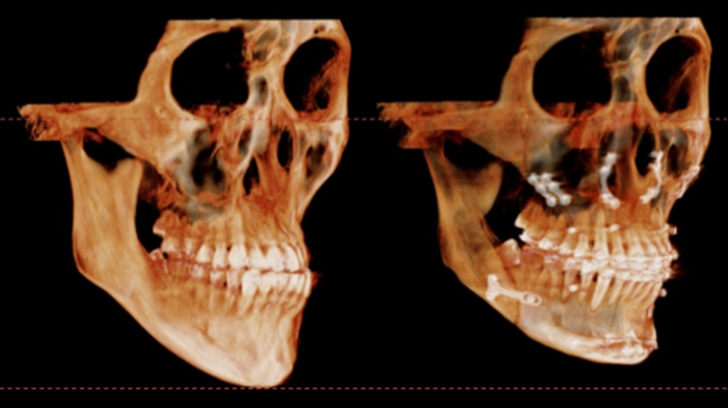

수술 3개월이 경과한 시점에 촬영한 CT입니다.

이식한 뼈는 자연스럽게 리모델링 되면서

거의 흡수 없이 잘 생착 된 상태로 회복하였습니다.